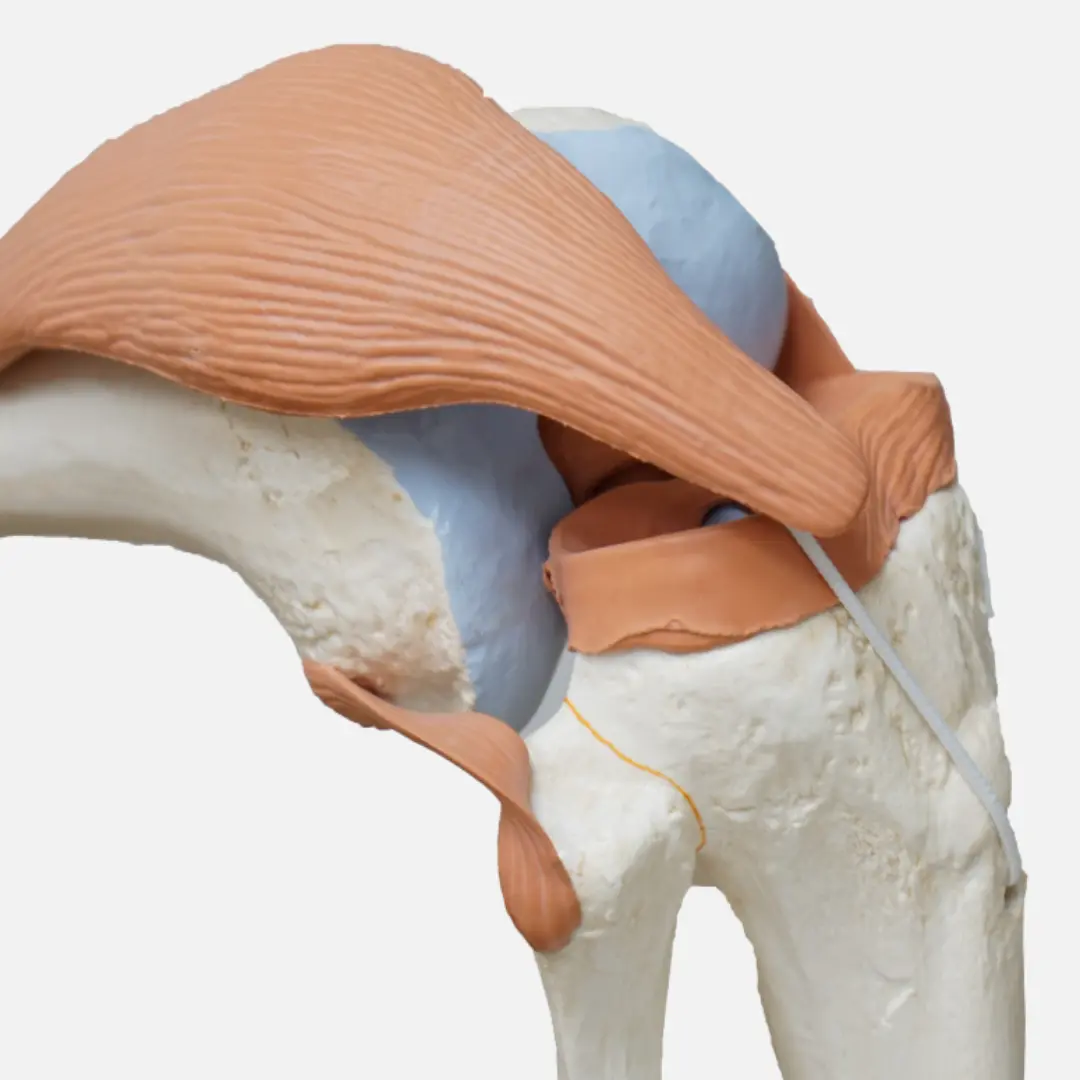

퇴행성관절염은 관절을 보호하고 움직임을 원활하게 하는 연골이 점진적으로 손상되거나 퇴행성 변화를 겪으면서 발생하는 만성 질환이에요. 연골은 뼈와 뼈 사이에서 충격을 흡수하고 마찰을 줄여주는 쿠션 역할을 하는데요. 나이가 들거나 과도한 사용, 외상 등으로 연골이 닳아 없어지면 뼈와 뼈가 직접 부딪히면서 염증과 통증을 유발하게 됩니다.

- 관절 운동 범위 감소: 연골이 손상되고 관절 주변 조직이 굳어지면서 관절을 완전히 펴거나 구부리기 어려워집니다.

- 관절의 외상 및 손상: 과거에 관절 부위에 골절, 인대 손상, 연골 손상 등의 외상을 입었던 경우, 이후 퇴행성관절염 발생 위험이 높아져요.